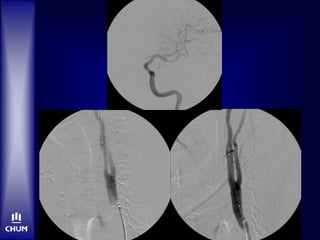

 20h55: IV t-PA bolus, 2/3 dose

 21h05: Angio suite. No sedation.

Case 2 –Mr. RD  20h55: IV t-PA bolus, 2/3 dose  21h05: Angio suite. No sedation.